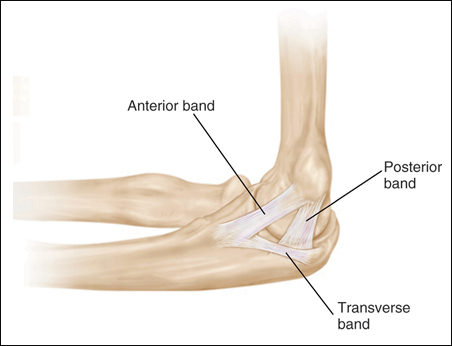

The medial ulnar collateral ligament is one of the primary static stabilizers of the elbow and is composed of three parts: anterior, posterior and transverse. The MCL provides resistance to valgus and distractive stresses. The anterior oblique fibers (of the anterior bundle) are the most important against valgus stresses. The posterior bundle is involved elbow contractures and releasing it can yield significant flexion gains, without creating valgus instabilit

AOL. POL. transverse ligament

Anterior oblique ligament: strongest most significant stabilizer to valgus stress.

- Anterior band: anterior band is primary restraint to valgus stress, exhibiting nearly isometric strain during elbow ROM. Primary restraint full extension to 85 degrees of flexion

- Posterior band: posterior band exhibits increasing strain during higher degrees of elbow flexion

Posterior oblique ligament: tight in flexion, important for valgus stability beyond 90 degrees of flexion

The transverse band plays no role in joint stability because it originates and inserts on the same bone.

UCL primary restraint to valgus stress from 30 to 120 degrees of flexion

at 25 degrees flexion the olecranon is unlocked from its fossa and the ulnar collateral ligament becomes the most important stabilizer. The posterior bundle is a fan-like thickening of the capsule that becomes taut as the elbow flexes well past 90 degrees and exhibits the most change in tension from flexion to extension.